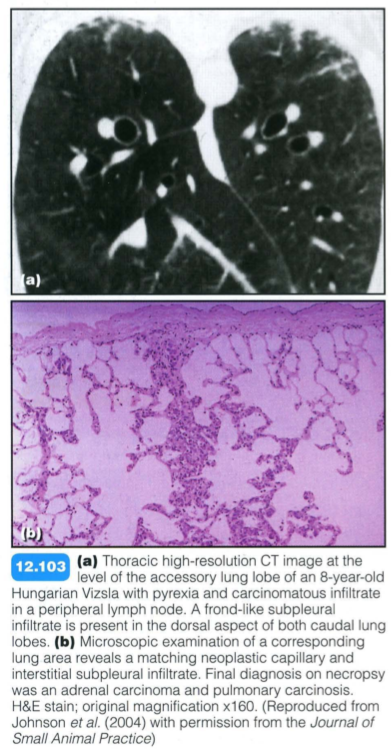

These are common with anaplastic mammary carcinoma and less common with salivary or pulmonary carcinoma or transitional cell carcinoma of the urinary bladder. Metastatic spread to the interstitium of the lung occurs via the lymphatic system and microvasculature. Neoplastic cells infiltrate the alveolar septal walls causing thickening, and may also cause thrombosis of small vessels.

Alveolar septal metastases and bronchoalveolar carcinoma: Radiographic findings are not specific but may include:

CT provides exceptional detail of the lung tissue and vasculature, and is very useful for diagnosis and staging of radiographically occult neoplastic disease. Imaging findings in dogs may include: